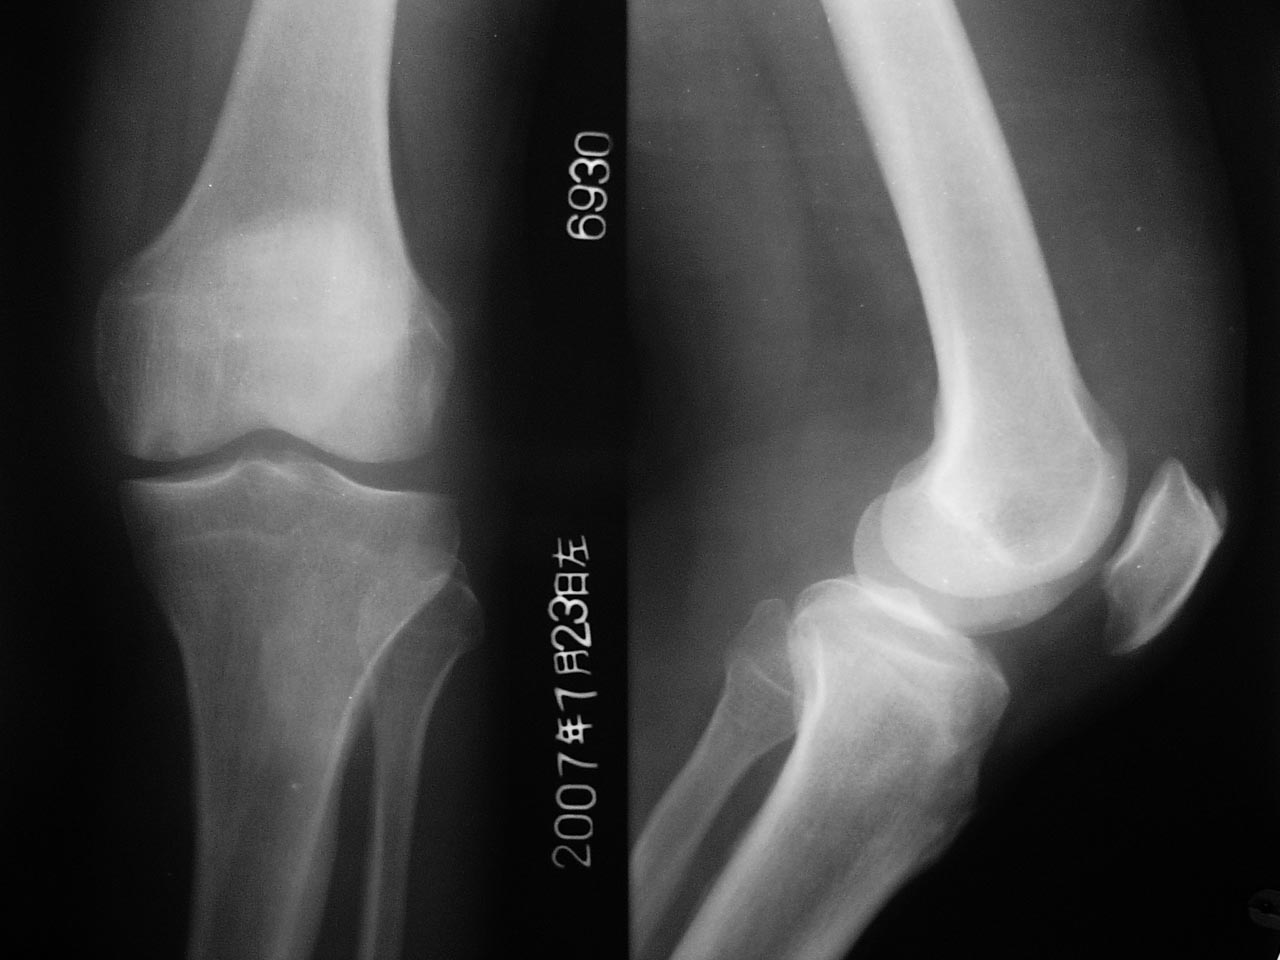

男,65岁,左膝关节痛疼半年,软组织稍肿,活动尚可。

1髌骨前上缘骨刺。

1髌骨前上缘骨刺

2考虑剥脱性骨炎,建议mri检查

1.左股四头肌肌腱钙化;

2.左股骨内侧髁下(关节面)局限性骨质密度减低区,性质?加上关节软组织肿胀,最好作进一步检查(mri)。

2左股骨内侧髁下(关节面)局限性骨质密度减低区考虑剥脱性骨炎,建议mri检

左髌骨前上方股四头肌]韧带钙化。

左股骨下内侧髁剥脱性骨炎。

考虑:1、左侧股骨内髁剥脱性骨软骨炎;

2、髌骨前上缘骨刺。

1、左髌骨前上方股四头肌]韧带钙化。

2、左股骨下内侧髁剥脱性骨炎。